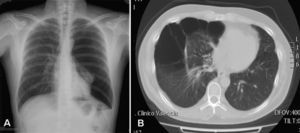

Up to 80% of patients with Birt–Hogg–Dubé syndrome have lung cysts, which may be asymptomatic for years.9,11,14–16 The number and size of the lesions varies from patient to patient, ranging from small cysts to bullae measuring several centimeters across, located mainly in the lung bases and at the subpleural level9 (Fig. 4). A relationship between size and volume of the cysts and the risk of pneumothorax has been reported—the larger the volume the greater the risk. The mean age of presentation is 38 years, with no clear predilection for either sex. Some studies suggest that male sex is a risk factor for spontaneous pneumothorax,17 whereas others report no such risk.9 Among patients who present lung cysts, approximately 20–30% have a history of pneumothorax, with a mean of 2 prior episodes.9 In addition, when patients with a history of pneumothorax are studied, the vast majority have multiple cysts. The right lung is more frequently affected, although both lungs can be involved in up to 23% of cases.9 In patients with Birt–Hogg–Dubé syndrome, the risk of pneumothorax is 50 times greater than in the normal population.16 The most frequent mutation in patients with a history of pneumothorax or lung lesions and Birt–Hogg–Dubé syndrome is c.1733ins/delC located in exon 119. Patients with certain mutations are at risk of developing larger and more numerous cystic lesions. Thus, the mutation in exon 9 confers a risk of developing a greater number of cysts, whereas mutations in exon 9 and 12 are associated with larger cysts.9 The pathophysiology of lung cysts is unknown but it may be that haploinsufficiency is enough to induce the development of these lesions, as is the case in skin tumors. In addition to the characteristic associations described above, in patients with Birt–Hogg–Dubé syndrome, there have been reports of adenomas and colorectal polyps, parotid oncocytomas, parathyroid oncocytomas, neural tumors, trichoblastomas, lipomas, angiolipomas, connective tissue abnormalities, chorioretinopathy, and nonrenal malignant neoplasms such as breast cancer, colorectal cancer, tonsil cancer, and lung cancer, and also skin cancers such as melanoma, basal cell carcinoma, squamous cell carcinoma, dermatofibrosarcoma, and leiomyosarcoma.18 Despite these reports, a significant association between Birt–Hogg–Dubé syndrome and these neoplasms has not yet been demonstrated, and further studies are needed.19 Some authors maintain that carriers of the c.1285dupC mutation have a greater risk of colon cancer.19